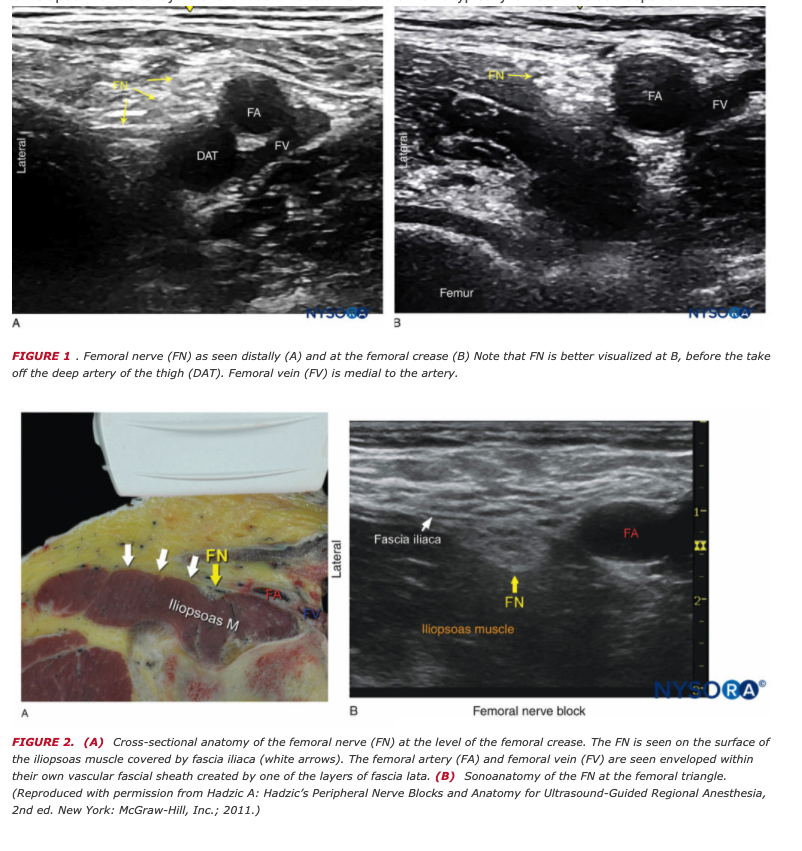

Femoral Nerve Block Anatomy

Identify the following block and structures